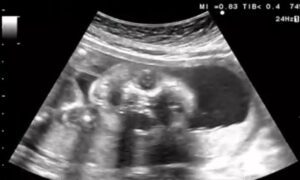

妊娠22週4日のエコー検査の際、画面に映し出された赤ちゃんはあくびをしていました。

エコー中は毎回元気に動き回っていることが多かったのですが、最後に大あくびを見せた赤ちゃんに、先生もママさんも「元気すぎるくらいだね」と笑ってしまったそうです。